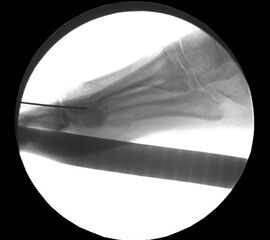

Es erfolgt dann die Osteotomie des Köpfchens im dorsalen ¼ des Köpfchens, parallel zur simulierten Bodenauftrittsfläche. Es ist streng darauf zu achten, dass es zu keiner Plantarisierung des Köpfchens kommt. Die Hohmann-Haken müssen so gesetzt werden, dass sie die Strecksehnen während der Osteotomie schützen. Während des Sägevorgangs ist eine entsprechende Stellungskorrektur der Hohmann-Haken durchzuführen um eine komplette Osteotomie zu gewährleisten. Der Winkel des Sägeschnittes bei MT II beträgt ca. 45° zur Schaftachse und nimmt im weiteren Verlauf zu den lateralen Metatarsalia auf ca. 20° ab. Die Osteotomien werden dementsprechend länger. Kommt es zu einer Verletzung der langen Strecksehne, muß diese dann wieder durch eine spannungsfreie Naht rekonstruiert werden. Dieser Schritt ist der entscheidende für den Erfolg der Operation und ist mit der entsprechenden Sorgfalt und Planung durchzuführen.

Darstellung des Sägeschnittes im dorsalen Drittel des Metatarsaleköpfchens.

Die Osteotomie wird nun mit einem Meißel Stärke 10 mm dargestellt, das mobilisierte Köpfchen nach plantar gedrückt. Durch eine leicht nach proximal abfallende Osteotomie erfolgt die Bestimmung der Verkürzung und das Ausmaß der Verschiebung des Köpfchens nach dorsal. Zur Vermeidung einer Plantarisierung des Köpfchens durch die Verschiebeosteotomie erfolgt ein 2. paralleler Sägeschnitt mit Resektion einer 2-3 mm dicken Knochenscheibe.